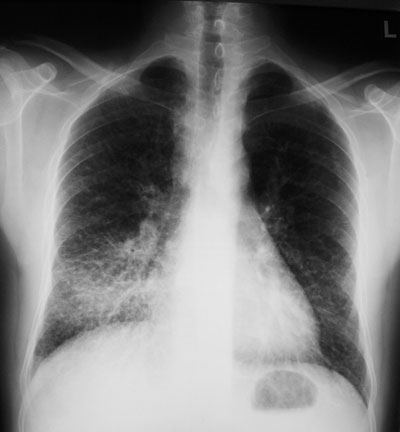

Ein 46-jähriger Patient konsultiert Sie wegen chronischem trockenem Husten seit zwei Monaten und einem Gewichtsverlust von 6 kg in derselben Zeit.

Dyspnoe verspürt er lediglich bei starker Anstrengung. Fieber wird verneint. Lungenperkussion und -auskultation sind unauffällig; im Gegensatz zum Röntgenbild:

Thorax pa

Wie würden Sie den Befund beschreiben?

Welche beiden folgenden Differentialdiagnosen sind aufgrund der Klinik und des radiologischen Befundes am wahrscheinlichsten?